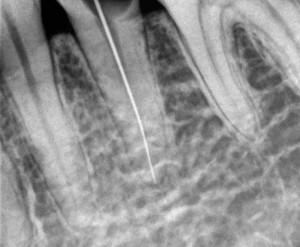

① 虫歯を全て削ります。歯の根っこの中には歯髄があり、歯髄は虫歯菌により感染を起こしているため、細い針のような器具で歯の根っこの先まできれいに歯髄を取り除きます。

② 神経をきれいに取り除いたら、消毒薬を入れ、仮フタをして1日目は終わります。

歯の根っこの先で神経を切っているため、根っこの先に小さな傷口があるような状態となります。

③ 歯の根っこの中の消毒が完全に終わり、症状もなければ、防腐剤(充填材)を隙間のないようきれいにつめます。

④ 土台(コア)をいれて、虫歯を取って空洞になっている歯を補強します。

⑤ かぶせものを入れて治療が完了します

治療前:大きな虫歯です